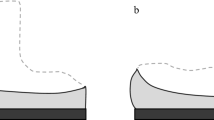

Preoperative and postoperative lateral radiograph of all 265 knee joints were used for radiological evaluation. Radiographs measurements were performed using the Picture Archiving and Communication Systems (PACS: Carestream Health, Rochester, New York, USA). Measurements were recorded to a precision of 0.1 mm and 1°. Measurements were performed using a similar method to previous authors [12, 18, 40], where PTS is the acute angle between the tibial plateau in the sagittal view, and the line perpendicular to the tibial mechanical axis (Figs. 1and 2); PCO is the perpendicular distance of the posterior-most aspect of the femoral condyle from a projection of the posterior femoral line (Figs. 1and 2); FSA is the acute angle between the cut surface of the posterior femoral condyle and the anatomical axis of the femur (Fig. 3a, b).